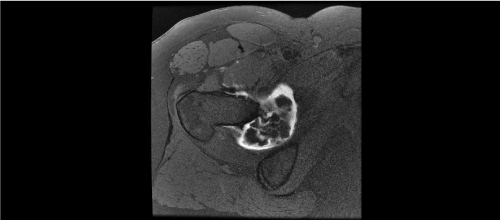

Four of our patients’ preoperative pelvic radiographs (66.6%) showed no calcifications, which made diagnosis difficult (Figure 1A, 1B). All patients’ preoperative MRI showed synovial hyperplasia and cartilaginous masses, which highly suggested the diagnosis of chondromatosis (Figures 2a, 2b).

Figure 1a. Plain radiograph (Left) show negative ossified masses in right hip

Figure 1b. Positive calcified masses (Right) in right hip